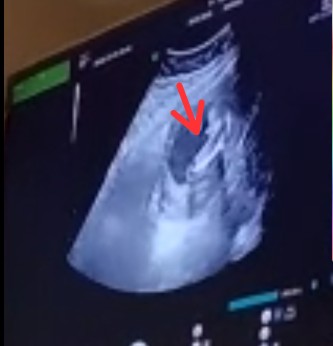

Ini insyaa allah boy bun, soalnya ada monasnya 😊

klo ini blm kliatan y bun girl atau boy ny